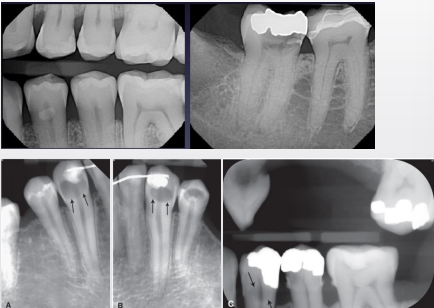

how do buccal and lingual caries show up in a radiograph

well-defined ovoid radiolucency

buccal/lingual caries may often be confused w occlusal caries due to superimposition, how can you sort of differentiate them

occlusal usually not as well-defined (pic shows B/L caries)

what is cervical burnout

artifact that can mimic caries commonly at or just apical to CEJ near alveolar crest

what is the cause of cervical burnout

x-rays passing tangentially through proximal area encounter less structure; shallow depression/concavity on M/D root surface can make area appear more radiolucent

when thinking of cervical burnout, thinner tooth structures absorbs fewer x-rays, so it will appear more ________________ (radiopaque/radiolucent) on the radiograph

radiolucent

caries or cervical burn out

burnout

caries or cervical burnout

caries